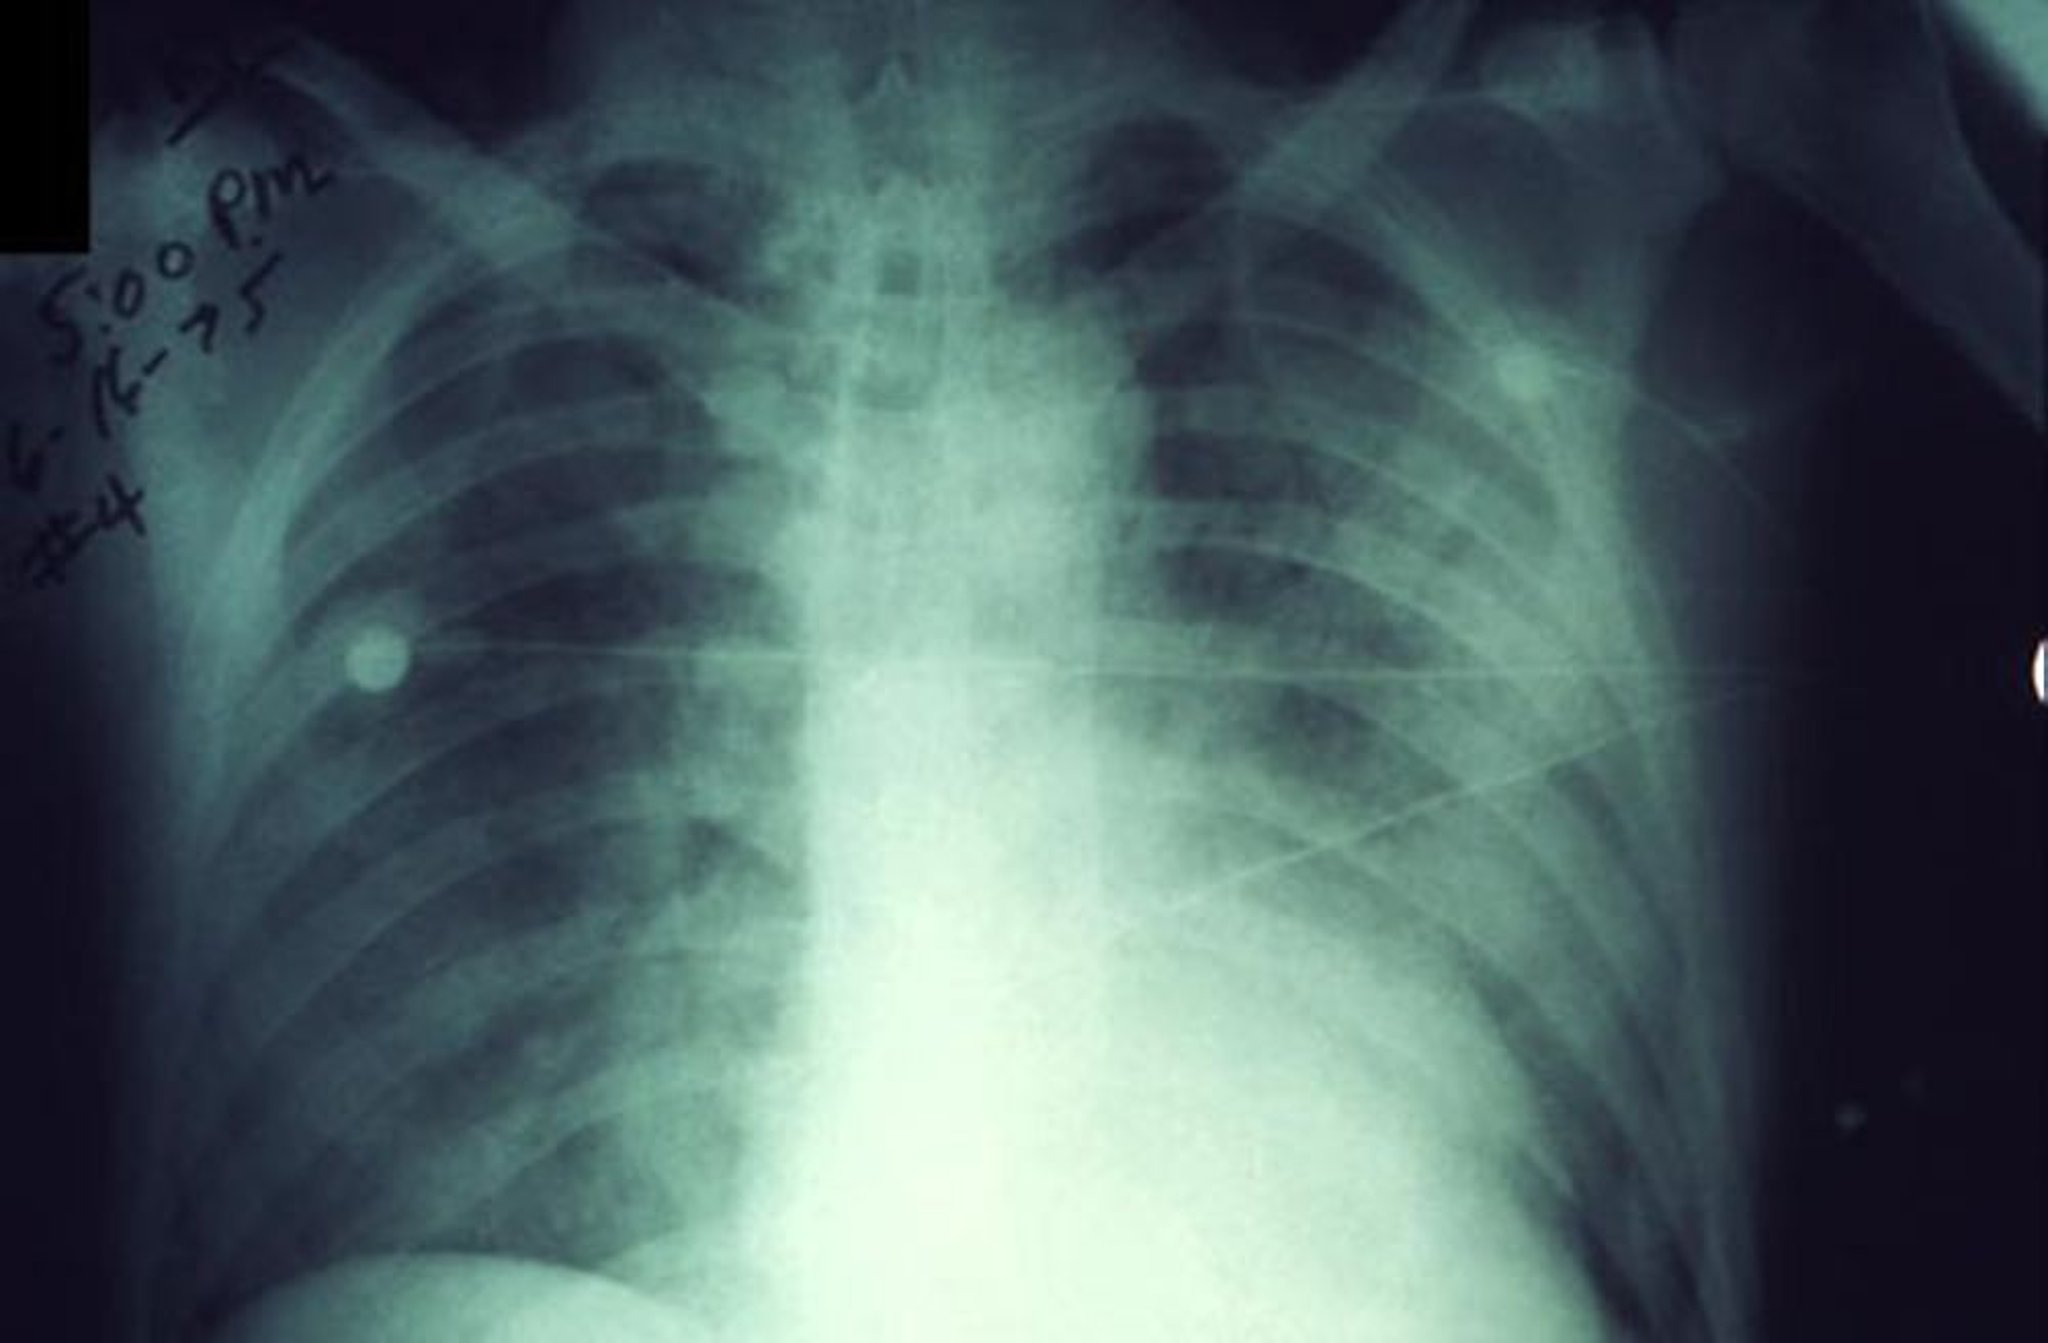

胸部X線では,当初は大葉性肺炎がみられ,その後は濃い浸潤影(consolidation)と同側肺の他領域または対側肺への気管支肺炎の進展がみられる。

肺の症状または徴候がみられる患者に対しては,胸部X線を施行すべきである(肺ペストでは急速に進行する肺炎像が認められる)。白血球数は通常10,000~20,000/μL(10~20 × 109/L)で,多数の未熟好中球を認める。